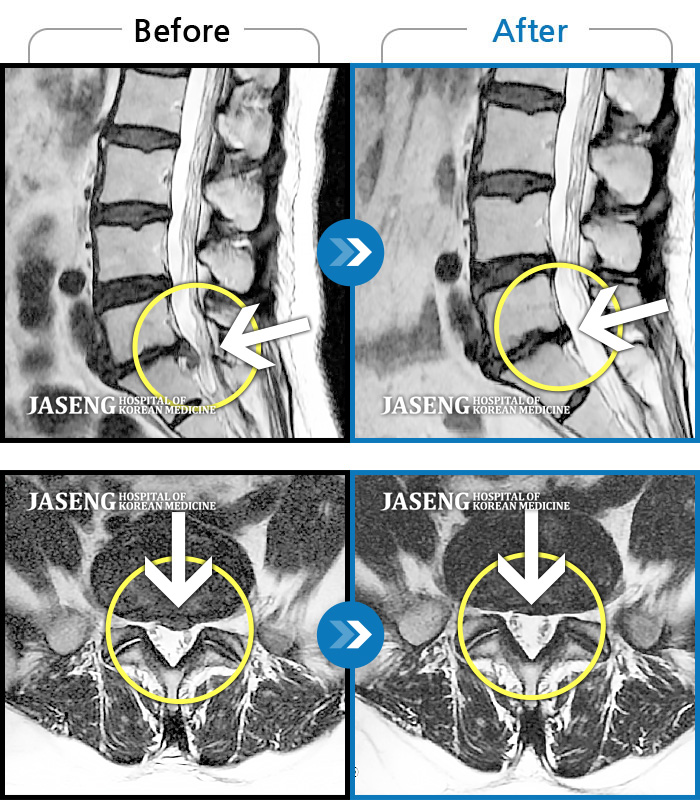

MRI 치료사례

허리가 펴지지 않는 상태로 진통제 없이는 보행이 불가능한 상태